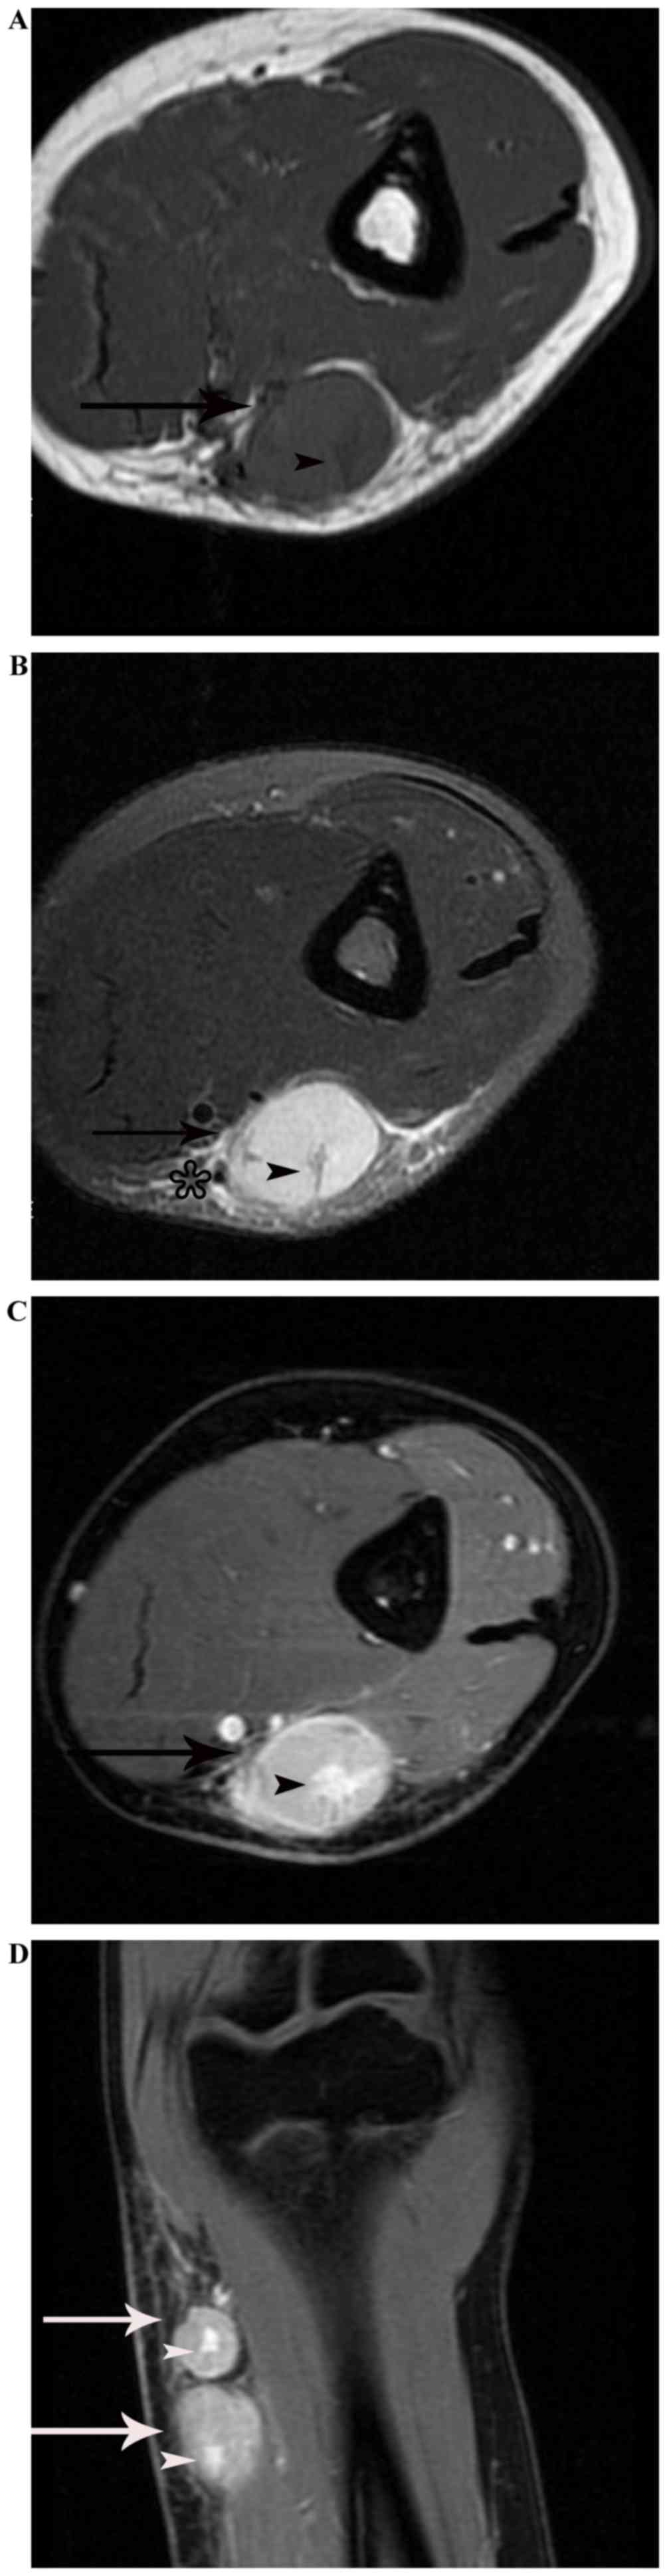

In total, there were 17 enlarged lymph nodes identified in 10 cases, of which 12 nodes were scanned on enhanced MRI, 3 on enhanced CT, and 2 on enhanced CT and MRI. Among them, 13 nodes were located at the elbow, 2 in the neck, 1 in the groin and 1 in the axilla. Multiple lesions were identified in 4 cases, and singular lesions in 6 patients. All the lesions were round, well-delineated nodes or nodules. The size of the enlarged lymph nodes ranged from 0.8–3.0 cm. On the CT scans, all the 5 nodes identified exhibited relatively inhomogeneous isodensity to muscle, with patchy or astral low density in the center. Following enhancement, 2 of the 5 nodes demonstrated marked heterogeneous enhancement, with no enhancement of the patchy low-density central areas, 1 of the 5 nodes displayed heterogeneous enhancement with progressive ‘spoke-wheel-like’ (defined as radiating enhancement from the center) enhancement of the patchy low-density area (Fig. 1), and the other 2 nodes demonstrated heterogeneous enhancement with peripheral flower ring reinforcement of the astral low-density area, also known as the ‘rose flower’ sign.

Figure 1.

Lymphadenopathy in a 57-year-old man with cat-scratch disease at the intermediate stage in the left neck. The node (arrow) displays heterogeneous enhancement with ‘spoke-wheel-like’ enhancement of the patchy low-density area on an enhanced computed tomography scan following intravenous contrast administration.

On the MRI scans, all the 14 nodes identified were homogeneously or heterogeneously isointense to muscle or with slightly increased intensity compared with that of muscle on T1WI, and homogeneously or heterogeneously hyperintense on fat-suppressed T2WI. Subsequent to enhancement, 8 of the 14 nodes displayed moderately homogeneous enhancement with no necrotic areas (Fig. 2) and 2 of the 14 nodes demonstrated marked heterogeneous enhancement with no enhancement of the necrotic central areas, which demonstrated patchy hypointense on T1WI and patchy hyperintense on T2WI in the center (Fig. 3A-C). Another 2 of the 14 nodes exhibited heterogeneous enhancement with marked enhancement of the astral hypointense area on T1WI and T2WI (Fig. 4A-C), and the other 2 exhibited heterogeneous enhancement with marginal petaloid enhancement of the astral hypointense area, namely the ‘rose flower’ sign (Fig. 5A-C). In addition, all 10 cases demonstrated general subcutaneous edema in the vicinity of the nodes.

Figure 3.

Lymphadenopathy in a 51-year-old woman with cat-scratch disease at the intermediate stage in the left elbow. (A) The node (arrow) indicates heterogeneous hyperintensity with patchy hyperintensity (arrow head) on a fat-suppressed coronal T2-weighted imaging scan, with general subcutaneous edema (star) in the vicinity of the node. (B) Following enhancement, the node demonstrates marked heterogeneous enhancement with no enhancement of the necrotic central areas (arrowhead) on an enhanced fat-suppressed axial T1-weighted imaging scan.

Figure 4.

Lymphadenopathy in an 18-year-old man with cat-scratch disease at the late stage in the left elbow. (A) The node (arrow) exhibits heterogeneous isointensity to muscle with astral hypointensity (arrowhead) on T1WI, and (B) heterogeneous hyperintensity with astral hypointensity (arrowhead) on fat-suppressed T2WI, with general subcutaneous edema (star) in the vicinity of the node. (C) Following enhancement, the node (black arrow) exhibits heterogeneous enhancement with marked enhancement of the astral hypointense area (black arrowhead) on an enhanced fat-suppressed axial T1-weighted imaging scan. (D) The two nodes (white arrow) demonstrate heterogeneous enhancement with marked enhancement of the astral hypointense area (white arrowhead) on an enhanced fat-suppressed coronal T1-weighted imaging scan.